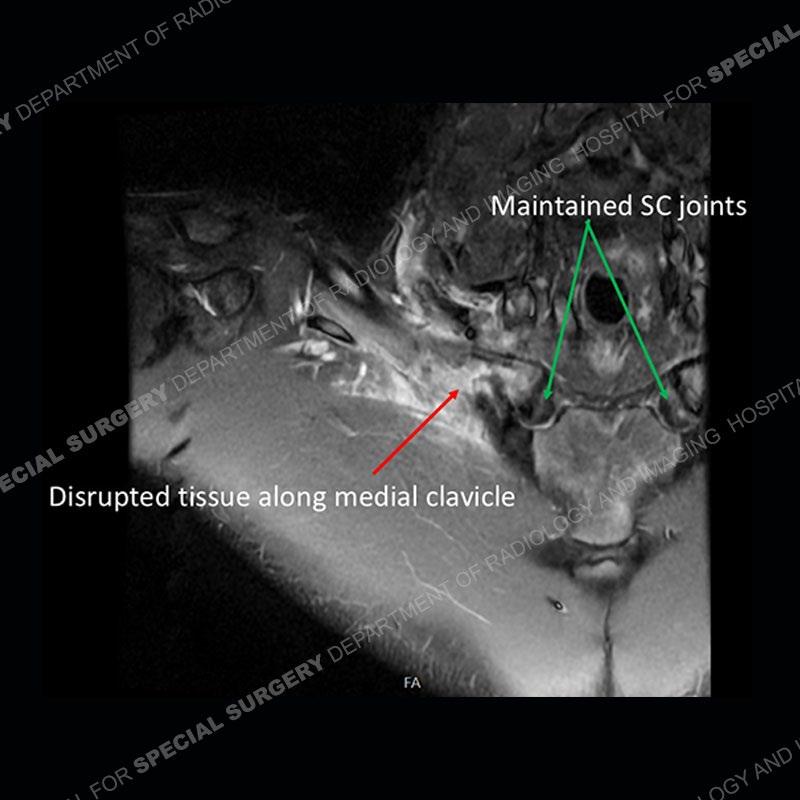

Subsequent imaging of the chest shows disruption of tissue along the medial aspect of the right clavicle and a deep insinuation of the bone along the medial aspect of the right clavicle. This is made more conspicuous with comparison to the left side. The edema pattern of the clavicle and the edema/hematoma of the subclavius persist.

The subsequent imaging shows almost complete resolution of the edema pattern of the right clavicle and edema/hematoma of the right subclavius. The tissue along the medial aspect of the clavicle shows interval scarring, particularly when comparing the sagittal PD images between the two studies.

The costoclavicular ligament (rhomboid ligament) extends from the undersurface of the clavicle to the first rib. The ligament attaches to the clavicle approximately 1cm lateral to the SC (sternoclavicular) joint. Injuries to the ligament are typically in the setting of an injury to the SC joint. Isolated injuries without SC joint injury are extremely uncommon with limited case reports in the literature.

The attachment of the ligament to the clavicle may have a normal variant with a deep fossa termed a rhomboid fossa. If this variant and its location are not known, it could mimic erosion or destruction of the bone. Adding more confusion is that the variant does not need to be bilateral or symmetric (as in this case where it is unilateral).